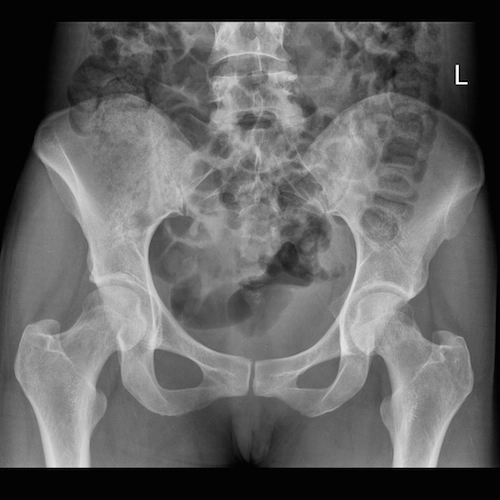

Tiếp cận X- quang xương chậu